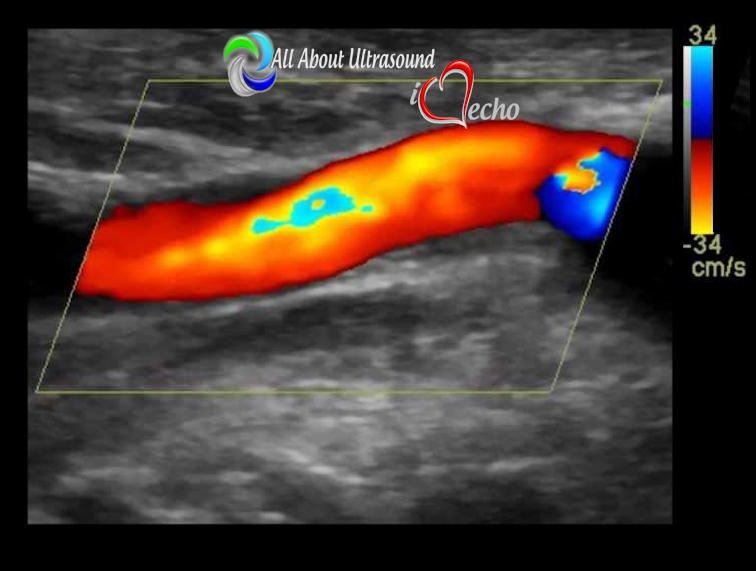

Designed for experienced sonographers ready to broaden their expertise, this program provides structured, step-by-step training in vascular anatomy, hemodynamics, and pathology, with a strong focus on real-world application and image interpretation.

Through weekly modules, case-based learning, and expert-led instruction, you’ll learn to perform and interpret arterial and venous Doppler studies, assess peripheral vascular disease, carotid, abdominal, and venous insufficiency exams, and apply advanced Doppler principles in clinical practice.

✔️ Hemodynamics & Doppler Interpretation

✔️ Vascular Pathologies, Plaque Assessment & Stenosis Evaluation